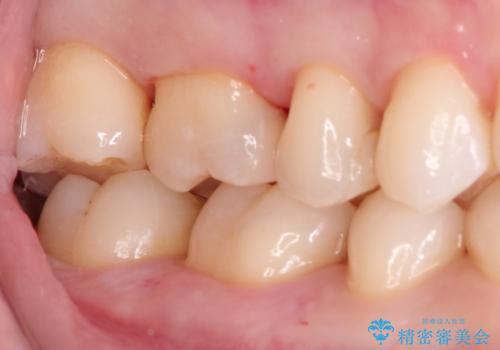

見た目が綺麗なセラミックインレー

セラミックインレーにて治療を行なっております。

e-max プレスインレーにて修復治療を行っているため適合性及び審美性の高い治療を行うことができます